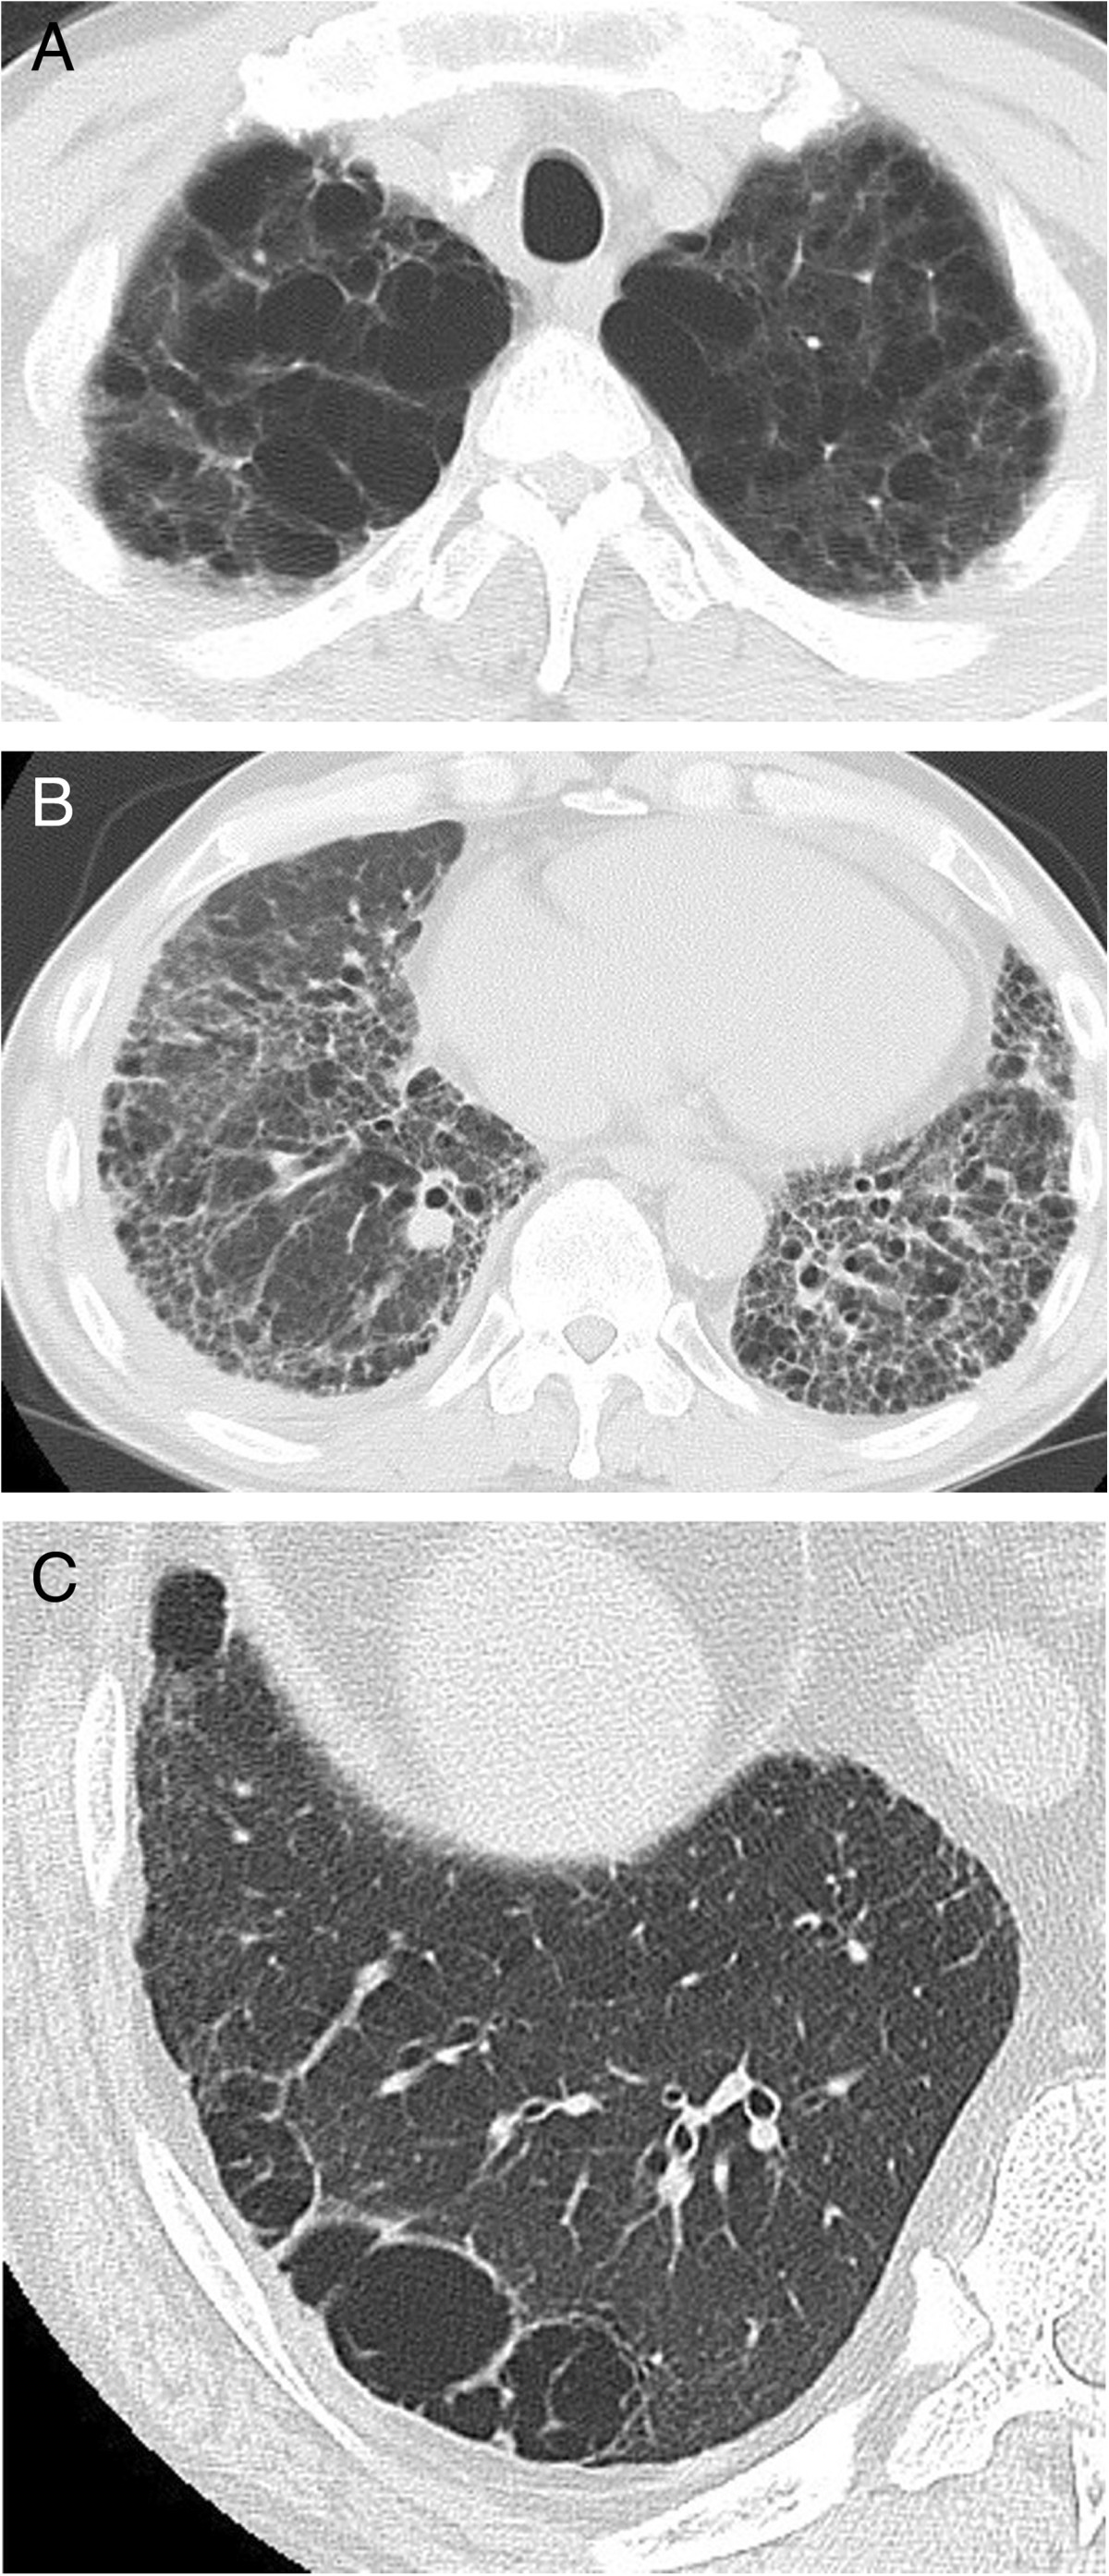

Representative cases of combined pulmonary fibrosis and emphysema Emphysema Autopsy Case Report Radiological patterns of the upper. We report an educational autopsy case of combined pulmonary fibrosis and emphysema. We reviewed 28 cases of fatal asthma tissue and identified the presence of pulmonary interstitial emphysema in 10% of the cases. We report an educational autopsy case of combined pulmonary fibrosis and emphysema. Radiological patterns of the upper. Here we show a rarely. Emphysema Autopsy Case Report.